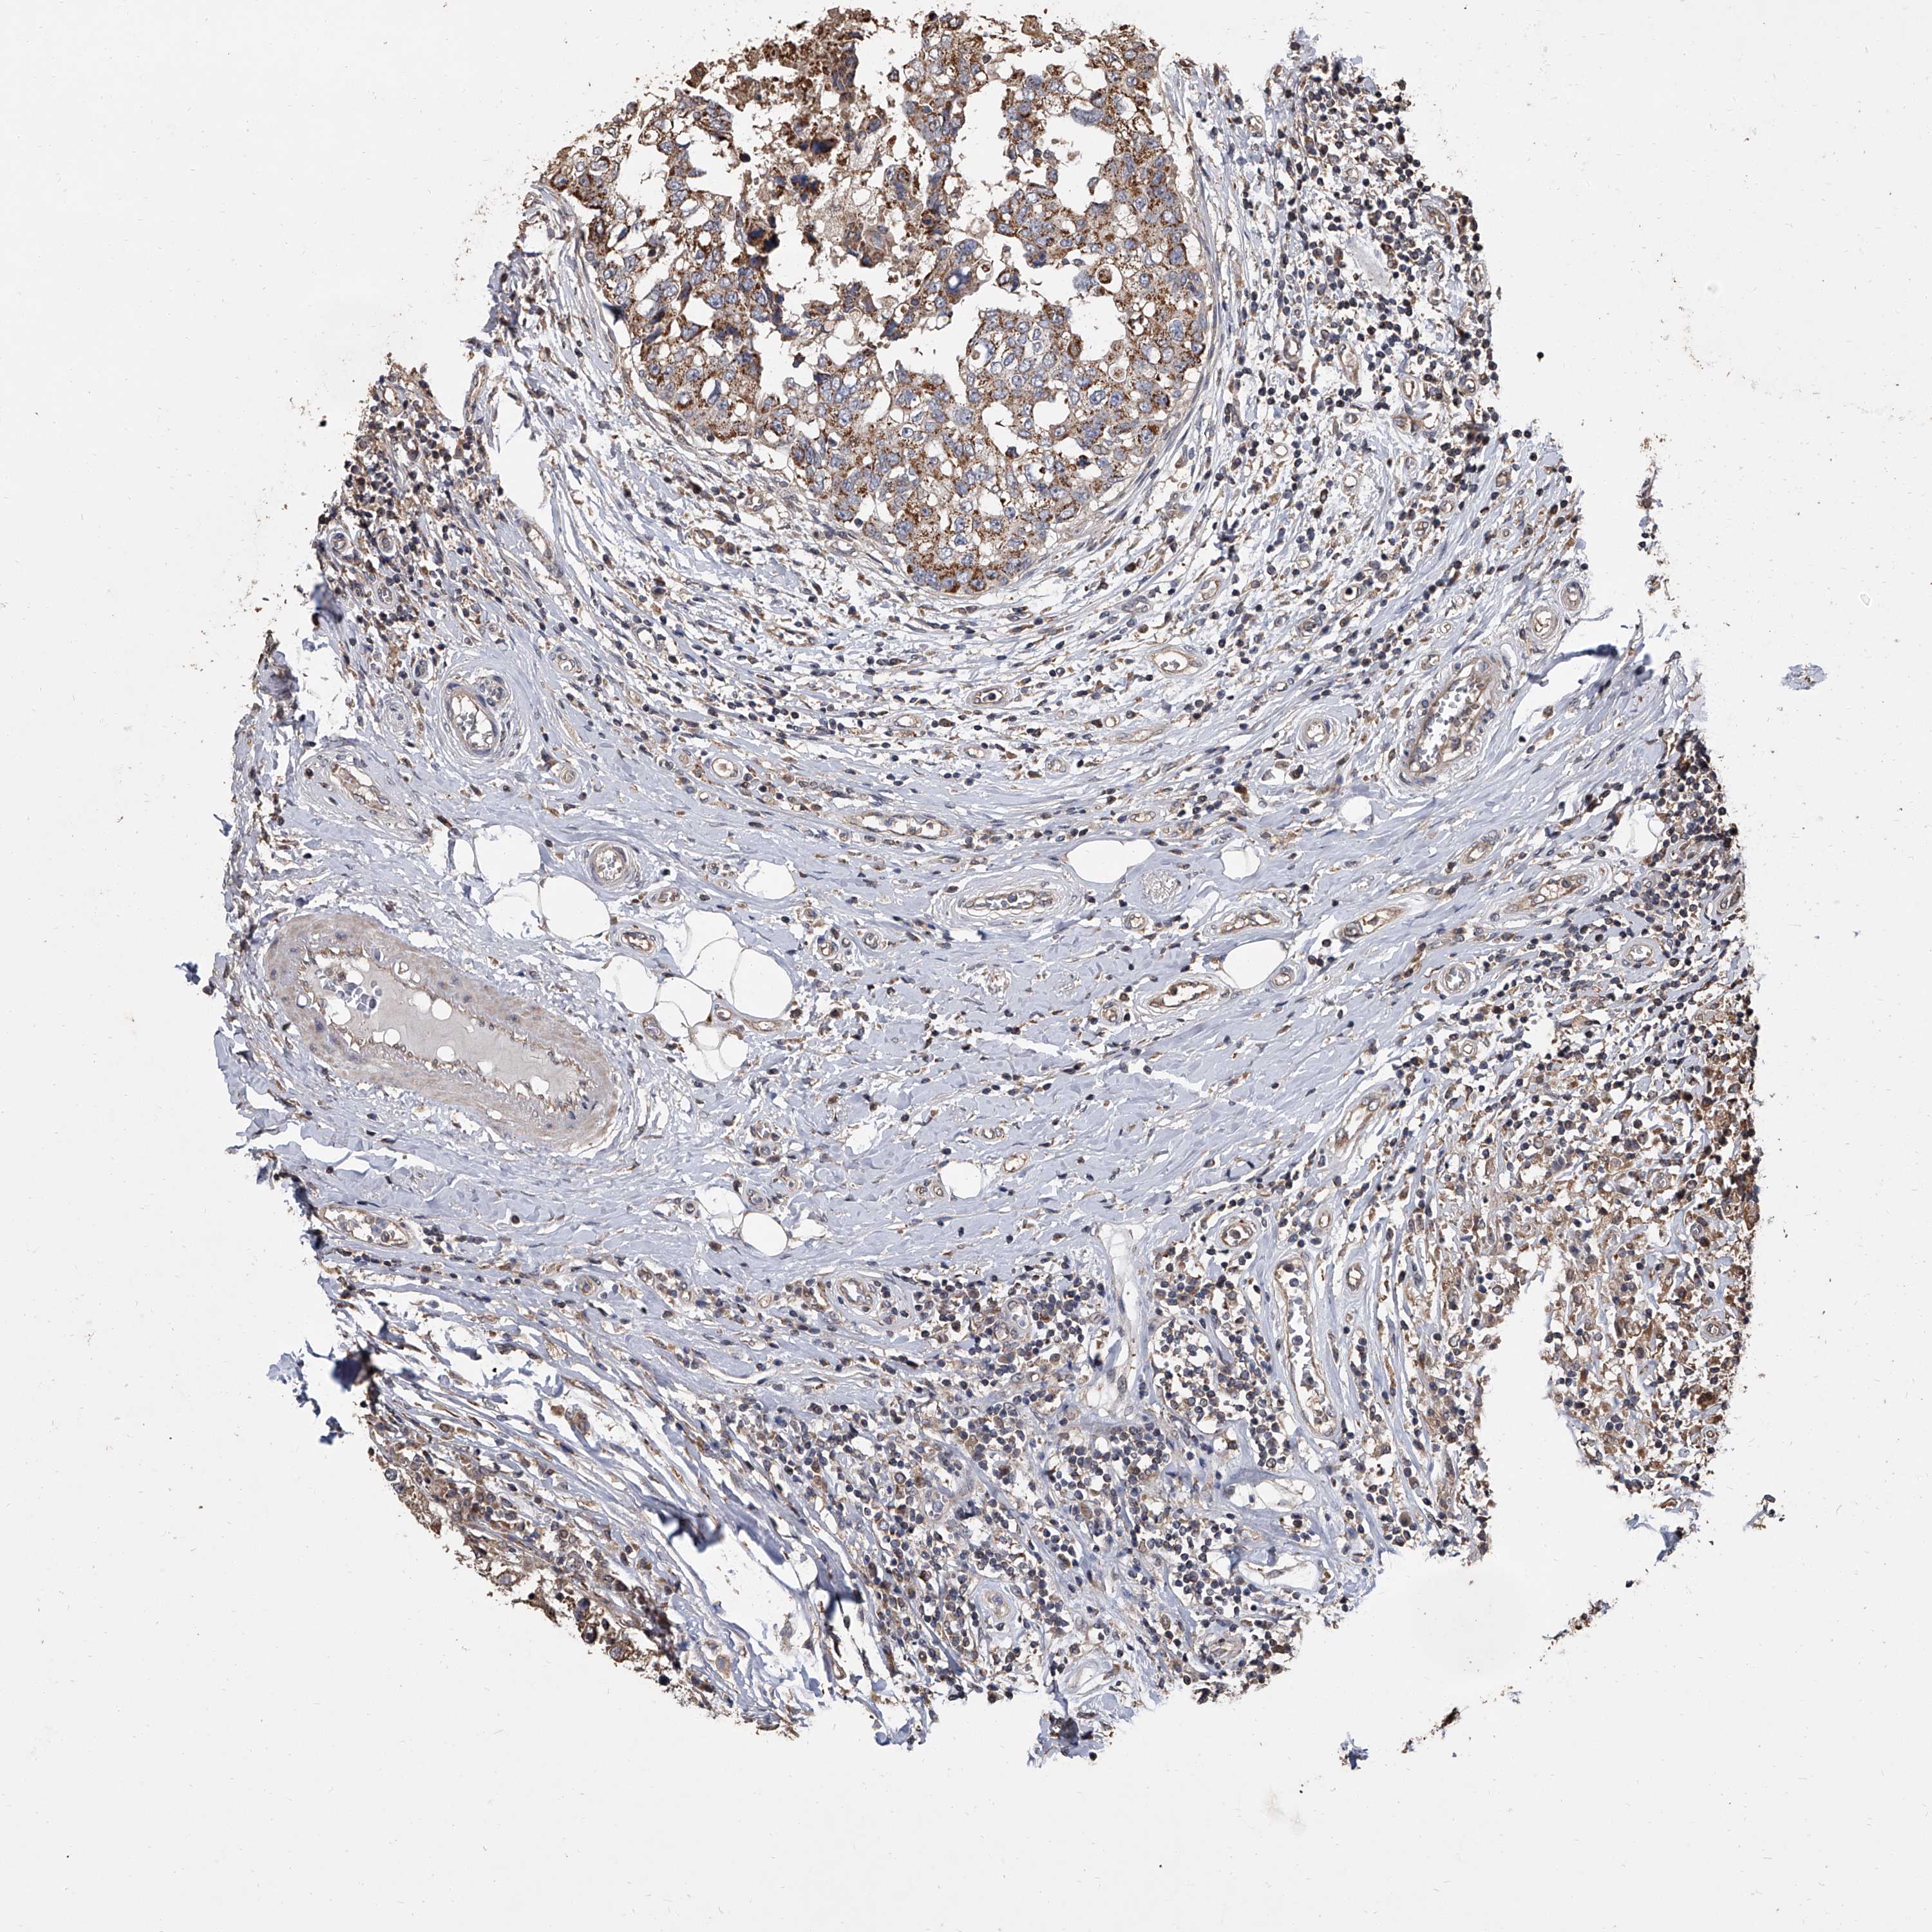

CANCER BREAST CANCER Show tissue menu

BRCA TCGA BRCA VALIDATION PROTEIN EXPRESSION